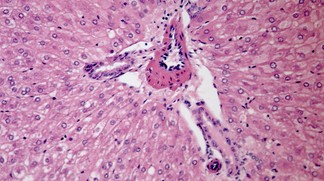

Les organismes vivants se sont adaptés au cycle du jour et de la nuit et disposent pour la plupart d’une «horloge circadienne», un véritable métronome cellulaire, dont les effets ne sont pas tous connus. Une équipe de l’EPFL et du Nestlé Institute of Health Sciences révèle que le foie produit ou libère des protéines selon un rythme dicté à la fois par l’alimentation et par cette horloge.